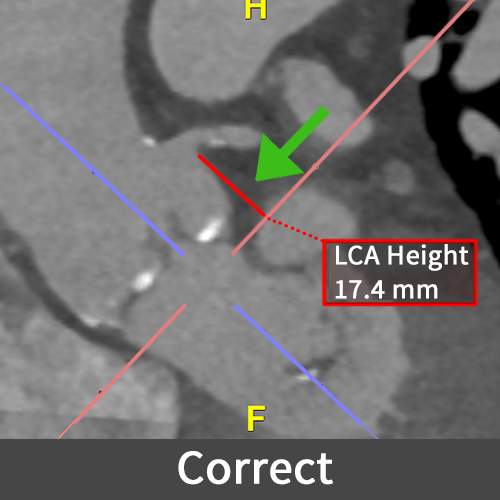

Transcatheter Aortic Valve Replacement

Transcatheter Aortic Valve Replacement (TAVR) is a minimally invasive procedure for replacing a diseased aortic valve in patients with aortic stenosis, involving measurement of the aortic valve annulus for accurate sizing of the replacement device.

This example shows an incorrect measurement of the left coronary artery (LCA).  If not corrected, this error can lead to significant complications of the TAVR procedure including valve mispositioning, causing coronary obstruction or sub-optimal sealing. This can potentially result in serious complications like myocardial infarction (heart attack), ischemia, or the need for additional surgical interventions.

Figure C (Right): The incorrect and correct measurements of the LCA height.